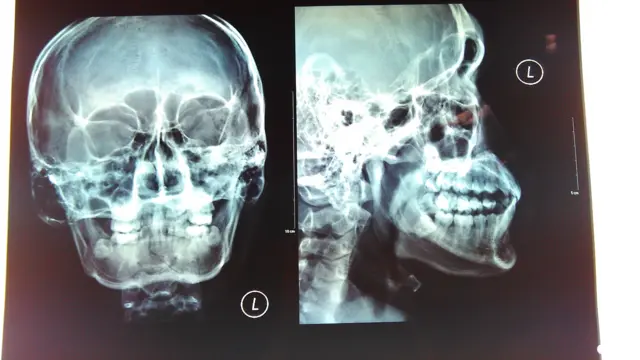

தலையும் மூட்டுப் பகுதிகளும் மனித உடலின் மிகவும் முக்கியமான பாகங்கள். அவை நன்கு பாதுகாக்கப்பட வேண்டியது அவசியம். மண்டை ஓடு முகத்தின் பாகங்களையும் மூளையையும் பாதுகாக்கிறது. நன்கு வளர்ந்த ஒரு மனிதரின் மண்டை ஓடு, 22 எலும்புகளைக் கொண்டிருக்கும். இவை, தலைப் பகுதி மற்றும் முகப் பகுதி என்று இரண்டாக வகைப்படுத்தப்பட்டுள்ளன.

கீழ்தாடையைத் தவிர மற்ற அனைத்து எழும்புகளுமே மிக மிகக் குறைவாக அசைக்கக்கூடிய வகையில் தான் இருக்கின்றன. இவற்றில் 8 எலும்புகள் மூளையைச் சுற்றி ஒரு பாதுகாப்பு உரையைப் போல் அமைந்துள்ளன. அதுபோக மீதமுள்ள 14 எலும்புகளும் முக அமைப்பில் இருக்கின்றன.

மூளையைப் பாதுகாப்பது, முப்பரிமாண பார்வையை வழங்குவதற்குரிய வகையில் கண்களுக்கு இடையில் இடைவெளியைத் தக்க வைப்பது, ஒலியின் திசை மற்றும் தொலைவை மூளை கணக்கிடுவதற்கு ஏதுவான அமைப்பில் காதுகளை வைத்துக் கொள்வது ஆகியவை தான் மண்டை ஓட்டின் ஆகப்பெரும் வேலைகள்.

மண்டை ஓட்டின் கடினமான தன்மை, உறுதியான மேற்புறம் ஆகியவற்றின் முக்கியத்துவமே மூளையைப் பாதுகாக்க வேண்டும் என்பதுதான். ஆனால், அத்தகைய பகுதியில், கடுமையான தாக்கம் ஏற்பட்டால் அங்குள்ள 8 எலும்புகளில் ஒன்றோ அல்லது அதற்கும் மேலோ உடையக்கூடிய வாய்ப்புகள் உண்டு.